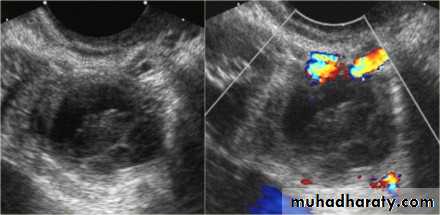

Polycystic ovarian syndrome (PCOS) is a chronic anovulation syndrome. Sonographic findings alone are not specific, and the diagnosis is made on the combined clinical, biochemical and sonographic grounds

The classic triad of PCOS is:

oligomenorrheahirsutism

Obesity

Ovaries

may show sonographic features of polycystic ovariesbilateral enlarged ovaries with multiple small follicles: 50%

increased ovarian size (>10 cc)

12 or more follicles measuring 2-9 mm

follicles of similar size

peripheral location of follicles: which can give a string of pearl appearance

hyperechoic central stroma

the ovarian outline may be slightly irregular